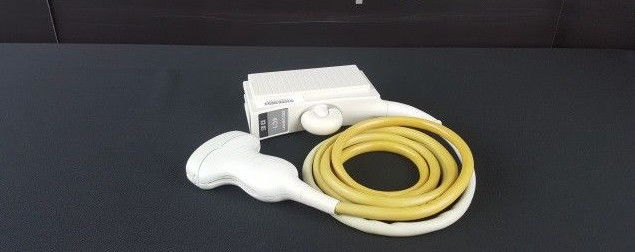

Acuson Probes

Showing 313 - 336 of 729 products